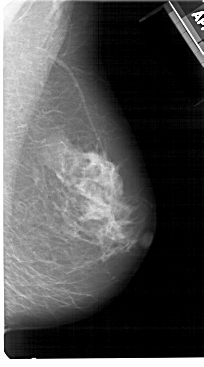

A_1512_1.RIGHT_MLO

RIGHT_MLO LINES 5491 PIXELS_PER_LINE 3046 BITS_PER_PIXEL 12 RESOLUTION 43.5 NON_OVERLAY